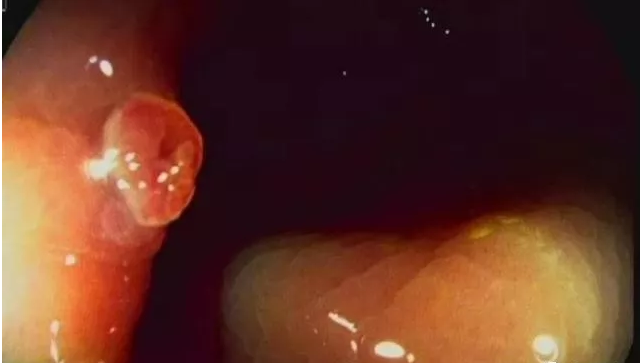

医生就按我们生长的部位给我们命名,譬如“鼻息肉”、“胃息肉”、“直肠息肉”、“膀胱息肉”等等。如果某一部位长有两个以上的息肉,就叫“多发性息肉”。

最阴险的是大肠息肉,经常多发分布,平时隐蔽生长,到时“摇身一变”就可成为结肠癌,只不过我的表面很脆弱,容易出血,病人发现血便就会去看医生,我这狐狸尾巴也就藏不住了,但是病人的病情往往也已经不轻了。

自从人们知道我们与癌症攀上了“亲戚”,人们对我们息肉的警觉性就越来越高了,动不动就用鼻镜、喉镜、膀胱镜、食道镜、胃镜、胆道镜、结肠镜等窥视我们的存在,把我们当成癌前病变加以及时彻底处理,使我们威胁患者生命的机会越来越少了。

随着医学技术的发展,已能够在内窥镜下用圈套器割除,或以电灼、激光来治疗,安全、有效、病人痛苦小,不再需要剖胸、剖腹,甚至不需要住院。